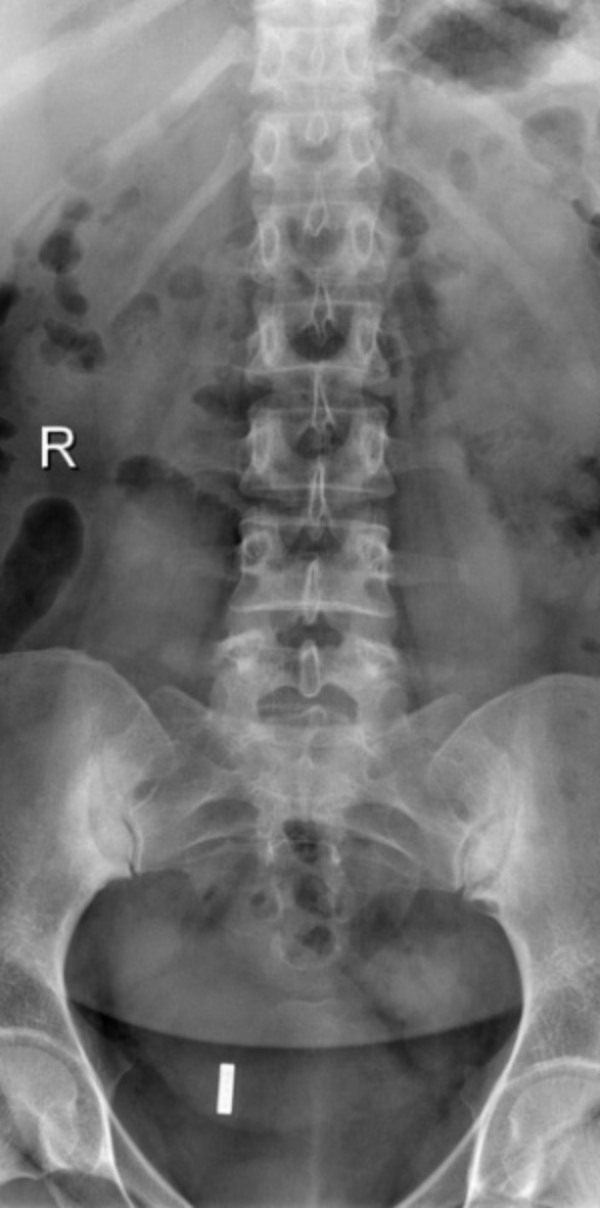

Tương tự như chụp X Quang, chụp CT (chụp cắt lớp vi tính) cho thấy các cấu trúc bên trong cơ thể. Nhưng thay vì tạo ra hình ảnh phẳng 2D, chụp CT sẽ chụp hàng trăm hình ảnh khi xoay quanh cơ thể để tạo nên hình ảnh 3D. Toàn bộ quy trình chụp CT có thể mất khoảng một giờ. (3)

Chụp CT cho thấy hình ảnh bất thường, các mức độ tổn thương khác nhau của khớp cùng chậu. Phương pháp này cũng có thể cho thấy tình trạng khe khớp cùng chậu rộng, xơ cứng trên bề mặt khớp, bào mòn khớp, dính một phần hoặc hoàn toàn khớp cùng chậu,… Dựa vào kết quả, bác sĩ sẽ chẩn đoán tình trạng viêm của khớp cùng chậu ở giai đoạn trung bình hoặc nghiêm trọng.